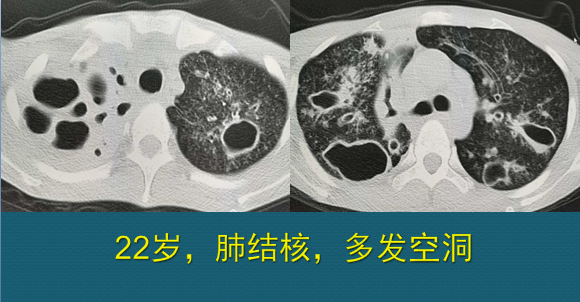

肺结核空洞ct

肺结核空洞影像学表现

胸部ct提示:双肺结核并空洞行成,右肺下叶实变.